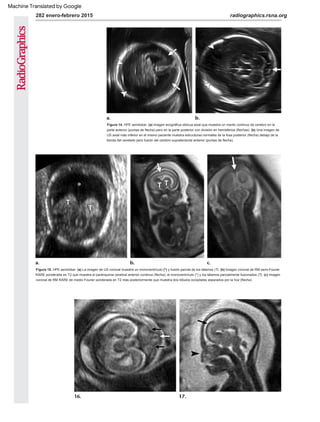

Figura 13. Alobar HPE. Imagen sagital de ecografía

Dop pler en color de una cabeza fetal que muestra el

signo de la “serpiente debajo del cráneo”: una sola

arteria cerebral anterior (flecha), también conocida

como arteria cerebral anterior ácida, desplazada

anteriormente para pasar por debajo de los huesos

frontales, en lugar de de entre los lóbulos frontales

como en un cerebro formado normalmente.

Figura 12. Alobar HPE. (a) La imagen de RM fetal

coronal muestra un monoventrículo (*), tálamos

fusionados (flechas) y tejido cerebral mínimo (puntas

de flecha). (b) Imagen sagital de RM semi-Fourier

RARE ponderada en T2 que muestra una parte media

de la cara aplanada (flecha) y la configuración de "bola"

de la corteza restante (puntas de flecha) que rodean el

monoventrículo (*). (c) La imagen coronal de EE. UU.

en el recién nacido confirma el monoventrículo único

(*), los tálamos fusionados (flechas) y un mínimo tejido

cerebral suprayacente (puntas de flecha).

Figuras 16, 17. Semilobar HPE. (16) Imagen de RM RARO medio-Fourier ponderada en T2 axial que muestra lóbulos occipitales separados con

características faciales anormales, que incluyen hipotelorismo (flechas negras) y una nariz tubular (flecha blanca), que demostró tener una sola fosa

nasal en imágenes obtenidas en otros aviones (17) Imagen sagital de RARE RARE de medio Fourier ponderada en T2 que muestra la morfología de

"bola", con el cerebro (flecha) rodeando el monoventrículo (*). Obsérvese el perfil anormal y aplanado (punta de flecha).